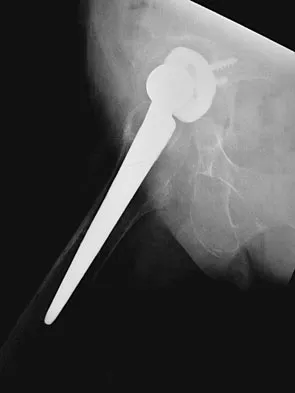

Figures 40a and 40b show the pre- and postoperative radiographs of an 82-year-old woman with bilateral hip pain who has had staged total hip arthroplasties. To minimize potential injury to the sciatic nerve at the time of surgery, the surgeon should

Explanation

To improve hip biomechanics and secure more suitable bone for acetabular fixation, the true acetabulum is often resurfaced in patients who have developmental dysplasia of the hip, thus lowering the hip center and lengthening the leg. Acute lengthening of more than 3 cm will place excessive tension on the sciatic nerve and require a femoral shortening to avoid sciatic nerve injury. The other maneuvers will not relieve sciatic nerve tension because of limb lengthening. Koval KJ (ed): Orthopaedic Knowledge Update 7. Rosemont, IL, American Academy of Orthopaedic Surgeons, 2002, pp 430-431.